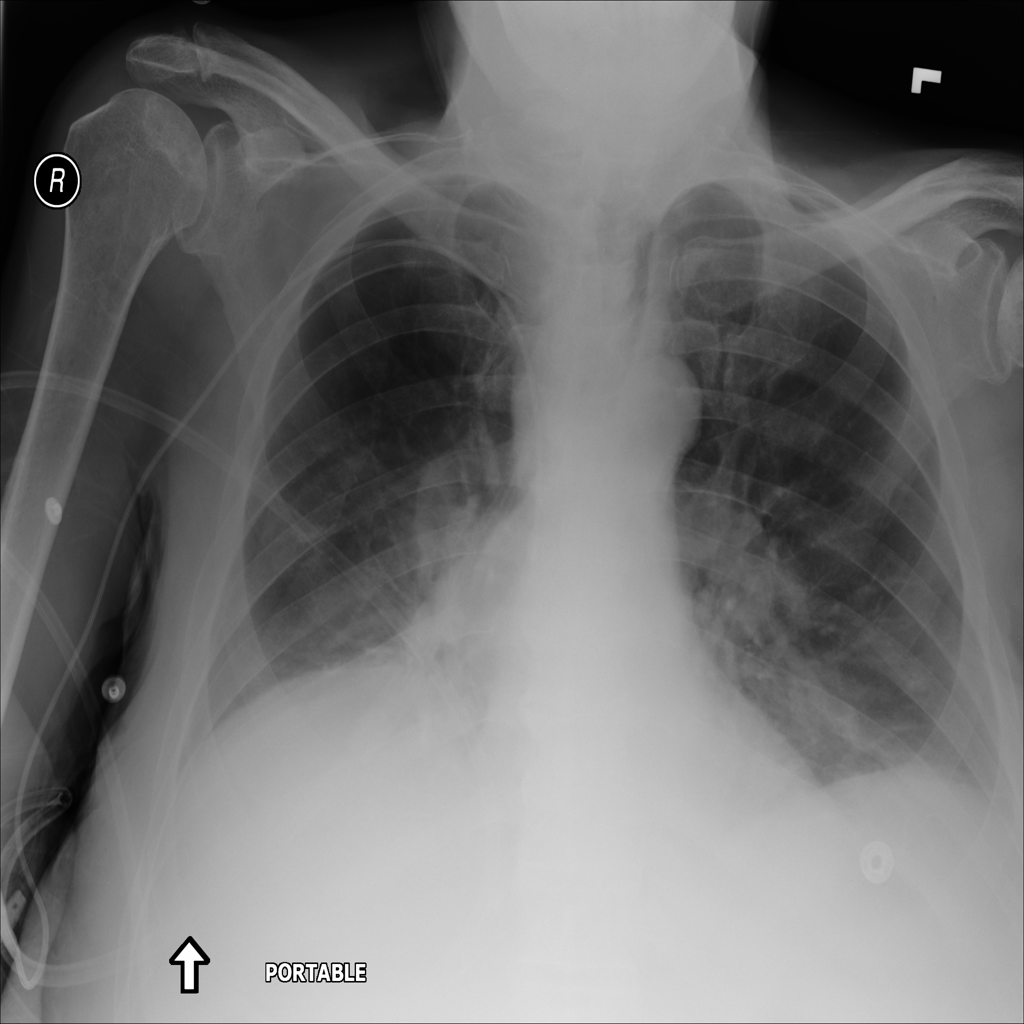

PAT-4639 · IMG-021Effusion

PAT-4639 · IMG-021

PA